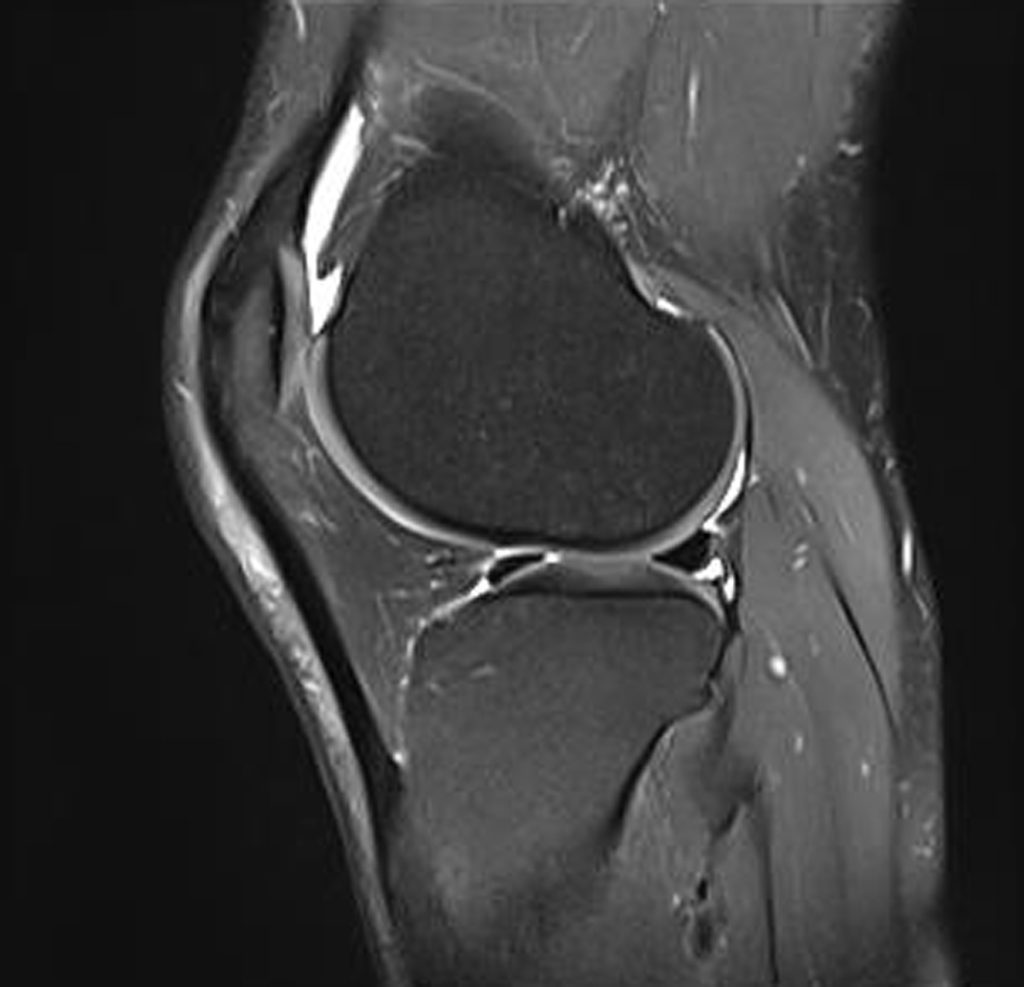

MRT-Termine können dauern und somit habe ich diesen erst in Mitte Februar 2026, allerdings bald danach einen Termin bei der Orthopädin am 19. Februar 2026. Der MRT-Befund ist ernüchternd:

Vorbekannter schräg horizontaler Einriss am Hinterhorn des Innenmeniskus, zunehmender Kontakt zur tibiaseitigen Oberfläche, die Rissbildung setzt sich horizontal in die dorsale Zona intermedia fort mit hier auch kleiner schräg verlaufender Risskomponente außenseitig. Ein winziger meniskaler Anteil diskret über die Tibiakante medialisiert. Intaktes Vorderhorn. Außenmeniskus intakt.

Unverändert geringer Erguss. Im Übrigen ergibt sich zur Voruntersuchung keine richtungsweisende Änderung […].

Unten eine Seitenansicht aus dem MRT. Im Gegensatz zum MRT von Ende August 2023 ganz oben auf der Seite, stehen die Knochen näher beisammen, das heisst, dass der Innenmeniskus an dieser Stelle in diesen 2,5 Jahren stark ausgedünnt wurde.

Die Orthopädin erklärt mir also, dass der Meniskus weiter in Längsrichtung einreisst und sich weiter ausdünnt. Dadurch kommen die die Knochen mehr und mehr in direkten Kontakt. So werden die Meniskuslappen zur Seite gedrückt. Nach Innen macht das kein Problem, sehr wohl aber nach aussen wo Drück und Reibung an der Gelenkkapsel entsteht. Dies erzeugt die Schmerzen. Die Kapsel ist eine Art Aussenhülle welche das ganze Knie unter der der Haut umgibt und nur hier gibt es nennenswerte Nerven. Man kann einen fehlenden Innenmeniskus (mein Fall) viel besser verkraften als Aussen weil innen die Knochenform besser zusammenpasst. Aussen bildet der Meniskus eine Art Zwischenstück, ohne dem die Knochen härter aufeinander treffen.

Ohne mich zu einer Meniskusteilresektion zu drängen, sagt mir die Orthopädin doch, dass es ohne OP nicht besser werden wird und erklärt mir auch den Ablauf solch eines arthroskopischen Eingriffs. Es ist ein minimalinvasives Verfahren, welches über zwei kleine Löcher an der Knievorderseite durchgeführt wird. Sie schweigt sich allerdings über die Dauer der Rekonvaleszenz aus. Ich gehe trotzdem im schlimmsten Fall von 3 Wochen Beschränkungen aus, die sich, wie oben öfters erwähnt, immer schlecht auf das ganze Knie auswirken.